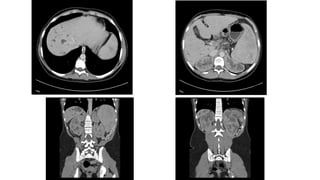

CT Scan

• Useful in identifying type IV & type V disease

• CT Cholangiography

• More sensitive for visualizing biliary tree

• More sensitive in detecting choledochal cysts

• Less sensitive to characterize pancreatic duct

CT Scan • Usefulin identifying type IV & type V disease • CT Cholangiography • More sensitive for visualizing biliary tree • More sensitive in detecting choledochal cysts • Less sensitive to characterize pancreatic duct